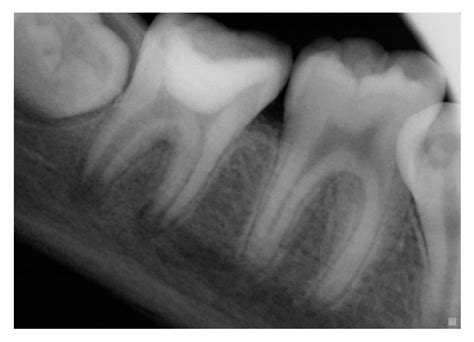

Los procesos patológicos que afectan a la pulpa, como ocurre con la caries dental, se suceden en distintas fases. En un primer lugar acontecen cambios inflamatorios en la misma, y mientras se mantenga vital, la afectación periodontal es mínima, pues como mucho podremos ver un engrosamiento del espacio periodontal o una lámina dura periapical difuminada. Sin embargo, a medida que la afectación pulpar avanza, los cambios que se producen a nivel del periodonto son notorios.

La necrosis pulpar sí que se asocia frecuentemente con inflamación del tejido periodontal, compartiendo mecanismos microbiológicos y etiológicos similares. Según la naturaleza de la microflora y la capacidad del huésped para resistir la infección, pueden generarse formas agudas (absceso agudo) y crónicas (reacción inflamatoria crónica) en cualquier sitio donde existe comunicación directa con la cámara pulpar. Una entidad puede evolucionar a la otra y, en ocasiones, puede ocurrir una transformación cística.

Diagnóstico Diferencial de las Lesiones Endo-Periodontales

Cuando analizamos los síntomas clínicos y los hallazgos radiográficos, muchas veces nos encontramos dificultades a la hora de saber si un diente tienen un problema periodontal o en su pulpa. La principal medida diagnóstica que tenemos para distinguir si una lesión es de origen endodóntico o periodontal es la prueba de vitalidad pulpar, que podemos llevar a cabo con un pulpo vitalómetro o con cloruro de etilo. Siempre habrá que tener en cuenta los falsos positivos y los falsos negativos de la técnica que empleemos para comprobar esa vitalidad.